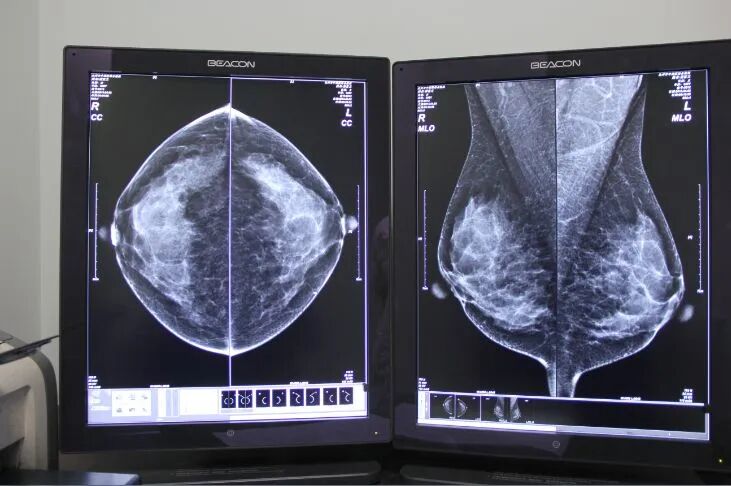

乳腺DR有什么优势?

乳腺DR是通过X线透射乳房并在胶片或荧光屏上成像,其敏感度较高,能显示乳腺内的微小钙化,可以检测出医生触摸不到的乳腺肿块,特别是对于大乳房和脂肪型乳房,其诊断性可高达95%